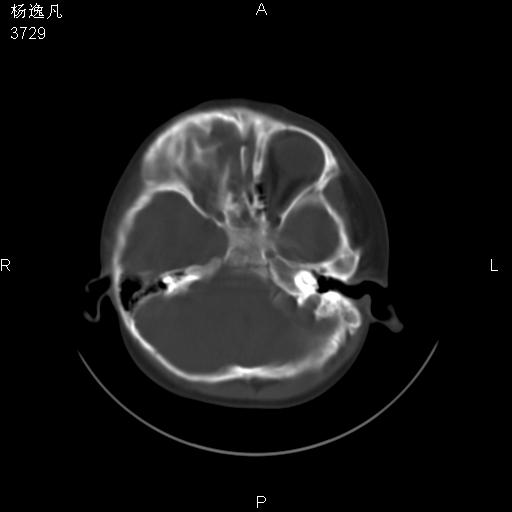

男性,5岁,面部受外伤,余无特殊

软组织窗

1、右面部及颞部软组织肿胀。

2、腺样体肥大。

头颅ct平扫未见明确外伤性征象,右侧面部及颞部软组织肿胀,后鼻腔软组织影增大,增厚,鼻咽顶部变窄,考虑鼻咽腺样体增值肥厚。